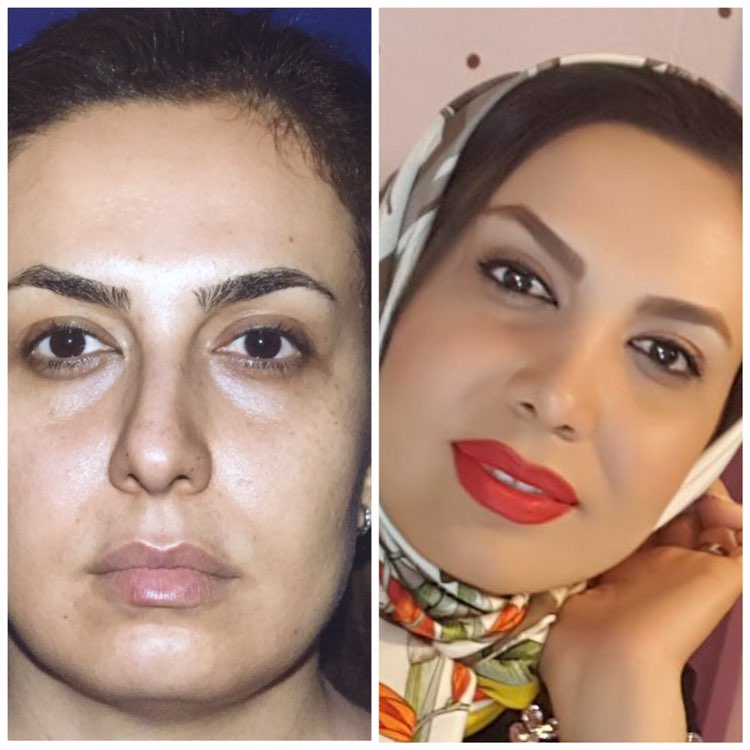

دکتر عیسی عبدی در رشت

دکتر عیسی عبدی در رشت

– متخصص جراحی فک , پلاستیک صورت و بینی

دکتر عیسی عبدی در رشت

جراحی فک , پلاستیک , صورت وبینی

تزریق ژل و بوتاکس